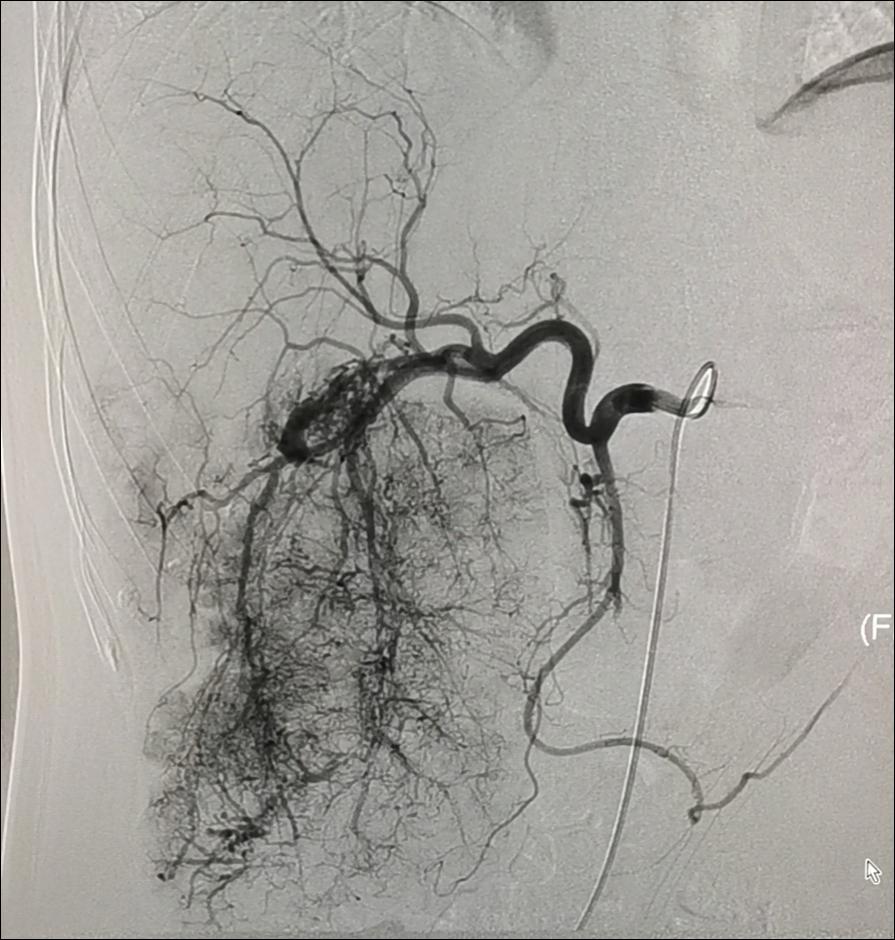

肝胆内科开展肝脏恶性肿瘤介入手术(包括经肝动脉灌注化疗栓塞术、经肝动脉置管持续化疗灌注术)、经皮经肝胆道穿刺引流术(PTCD术)、经皮经肝胆道置管术、经颈静脉肝内门体分流术(TIPS术)、胃冠状静脉栓塞术、部份脾动脉栓塞术(PSE)、肝脏穿刺活检术。

原发性肝癌TACE术前 原发性肝癌TACE术后